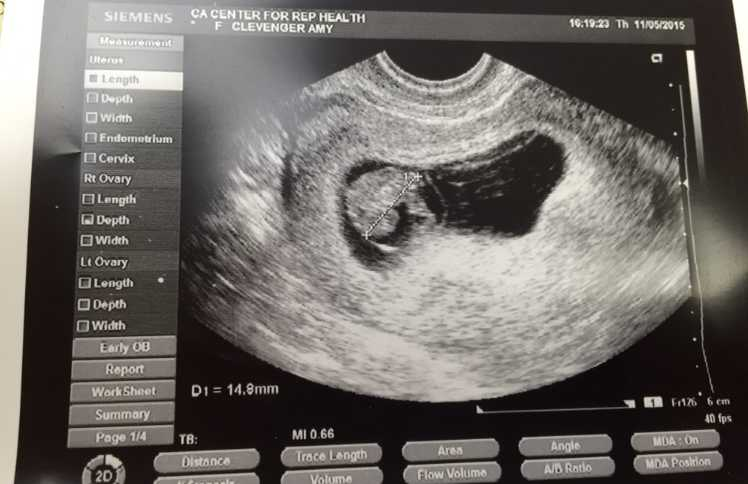

The treatment worked, and she gave birth to a healthy baby girl. After so many years of waiting, this moment felt like a miracle. She believed that her family was complete and that a natural pregnancy was almost impossible for her. She continued life as a new mother, focusing on caring for her baby and recovering from childbirth. But only three months after giving birth, she began feeling unusual symptoms. She felt tired, emotional, and not quite herself. At first, she assumed this was part of postpartum life. However, something made her take a pregnancy test even though she believed there was almost no chance of it being positive.

To her shock, the test showed two lines. She thought it had to be wrong. Her partner was also confused, thinking, “That’s not possible.” They went to the doctor for confirmation, and the results came back the same: she was pregnant again, completely naturally. Less than a year after giving birth to her IVF baby, she welcomed her second daughter into the world. Her story shows that while infertility is real and often difficult, surprises can still happen. Many people believe that if you need IVF once, you will always need help. But science tells us a different story. Research from University College London found that about one in five women who used fertility treatment for their first baby later conceived naturally. This doesn’t happen to everyone, but it is more common than many people think.